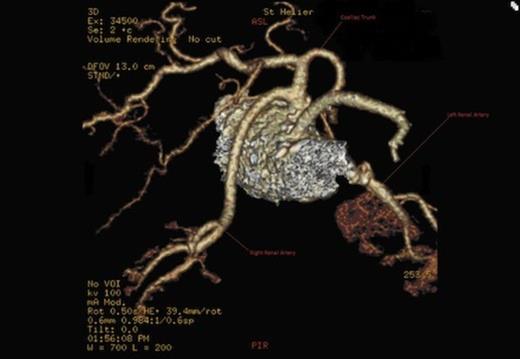

A CT scan revealed an aneurysmal distal thoracic aorta measuring 40mm and 49mm at the level of the diaphragm and of normal calibre at the left renal artery. The right renal artery very interestingly had its origin from the coeliac axis with no significant renal artery disease and the left renal artery showed calcific disease with post-stenotic dilatation at its ostium from the aorta. There were also no accessory renal vessels noted.